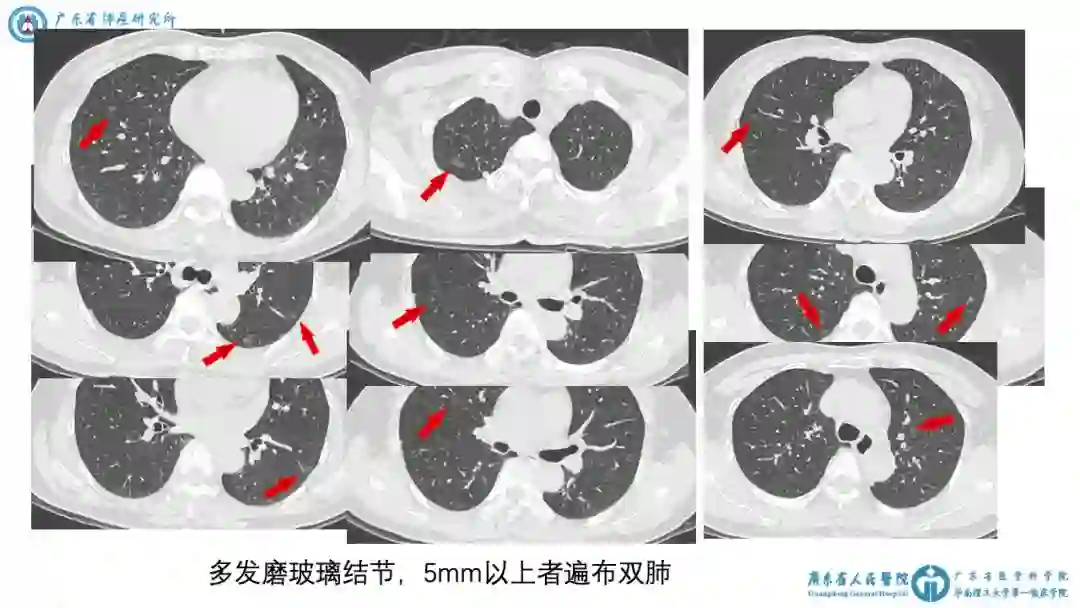

2)2018-10-16 胸CT平扫+增强:①左肺上叶斑片影,考虑慢性炎症。②多发磨玻璃结节,最大者左下肺8mm。③多发磨玻璃结节,5mm以上者遍布双肺。

3)病例特点:

中老年女性,偶然发现肺多发磨玻璃结节,无伴肺癌高危因素,伴有孤立实性病灶,考虑炎症。

初步诊断:肺多发结节,肺癌待排。